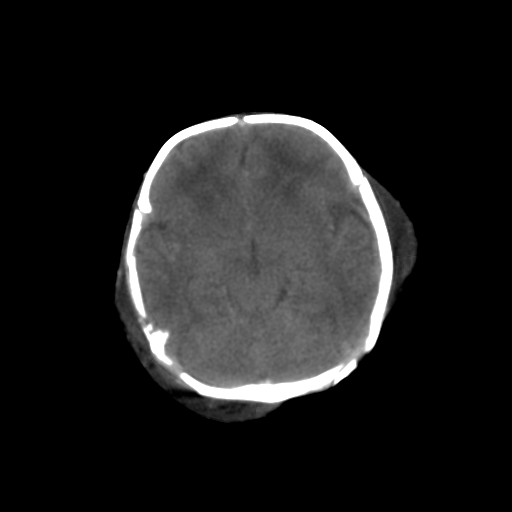

男,3天,患儿为剖腹产,生后嗜睡、拒乳。

1)考虑hie。2)sah?。3)右侧颞顶枕部及左侧颞顶部头皮血肿。

1、右侧颞顶枕部及左侧颞顶部头皮血肿。2、第五第六脑室。3、新生儿,脑白质密度还算可以,也无蛛血,不考虑hie。

脑室系统及脑沟裂闭塞,弥漫性脑密度减低,支持考虑hie,建议复查。右侧颞顶枕部及左侧颞顶部头皮血肿,另不除外胼胝体发育不良,复查